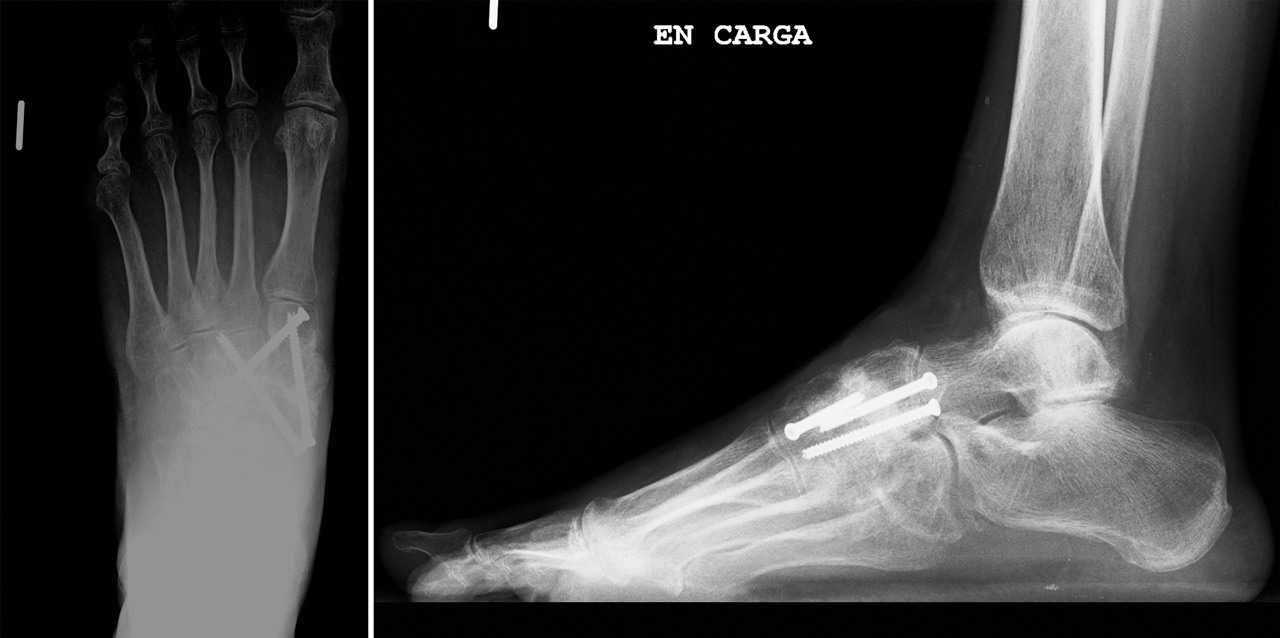

En el estudio mediante radiología simple en carga (Figura 2) se aprecia en la proyección dorsoplantar una desestructuración en la primera cuña con fragmentación y desplazamiento medial del fragmento proximal, así como cambios degenerativos escafocuneanos e intercuneanos. En la proyección lateral vemos un hundimiento de la columna medial a nivel transcuneano. En ambas proyecciones se aprecia una buena consolidación en el pie contralateral (clínicamente asintomático).

Figura 2. Radiografía preoperatoria.